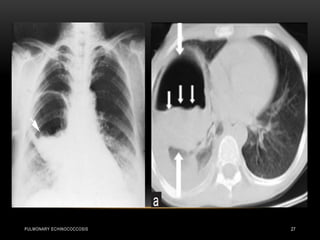

• ruptured hydatid cyst

(white arrows) and the

collapsed parasitic ...

• Sun rising sign or sun

set sign .

• (complete rupture)